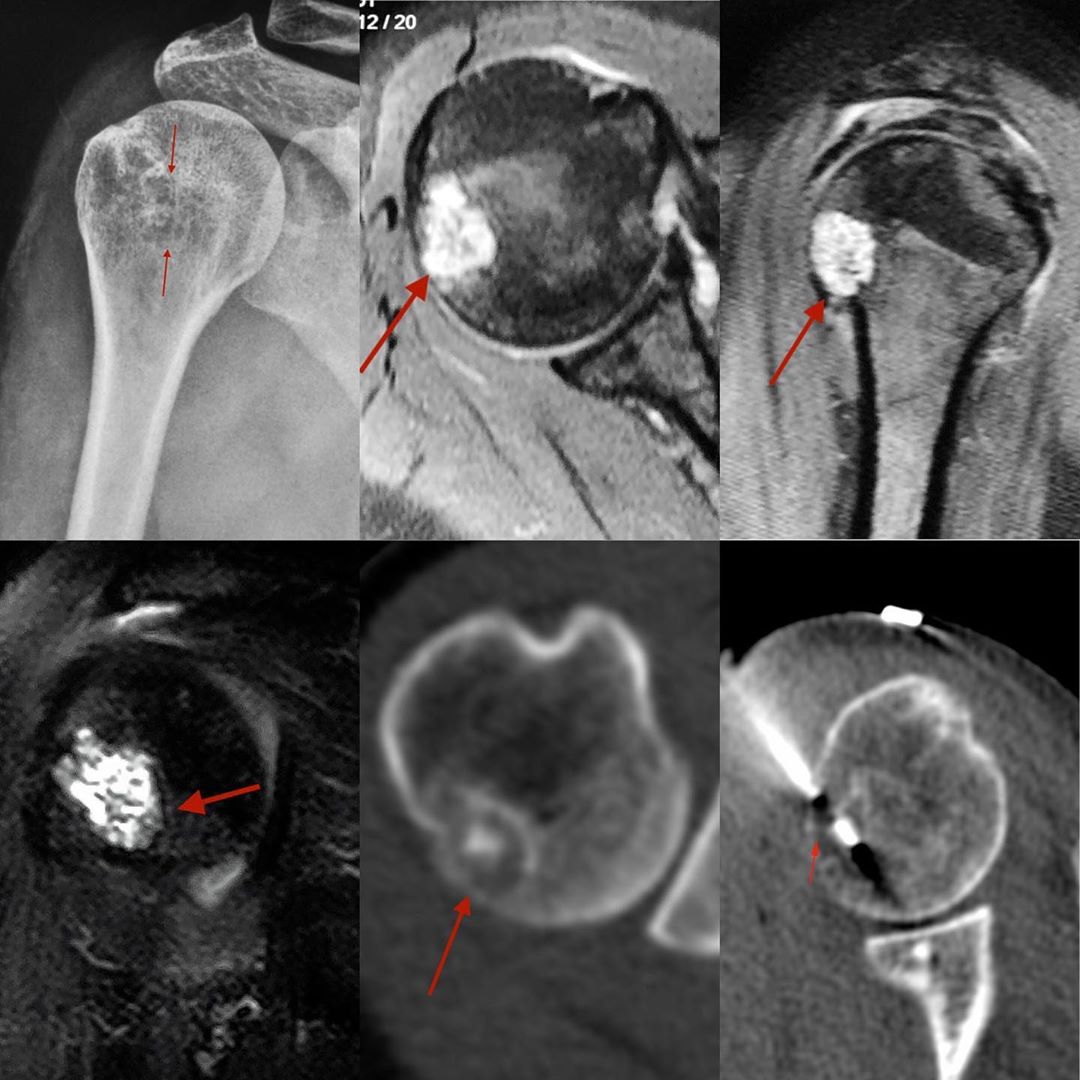

This is a 53-years old woman with pain in the right shoulder.

An MRI (PD fat sag axial and sagittal and STIR coronal) was performed, which showed a T2 bright lesion in the right humeral head without cortical break or marrow edema, findings absolutely characteristic of enchondroma and likely completely unrelated to her pain.

The CT scan at the time of biopsy also showed a sclerotic rim with a cartilage matrix. I asked them again whether they wanted me to continue with the biopsy and they insisted I do.

The diagnosis was benign cartilage containing tumor, which given the findings was consistent with an incidental enchondroma.